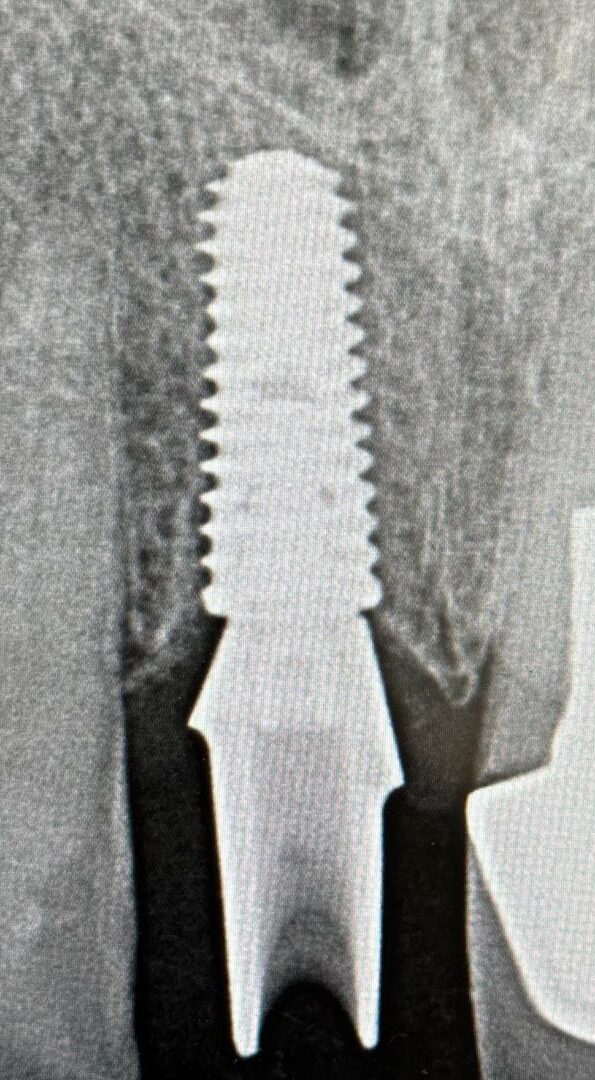

Single Front Implant

Upper right central incisor

Before

After